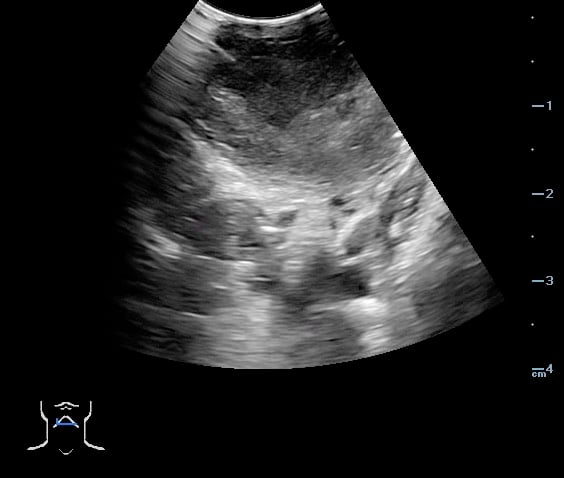

Video 27. PTA Aspiration - Complete aspiration verified by ultrasound:

- Figure 49 and 50. PTA Aspiration Resolution

Video 28. PTA - Aspiration Resolving